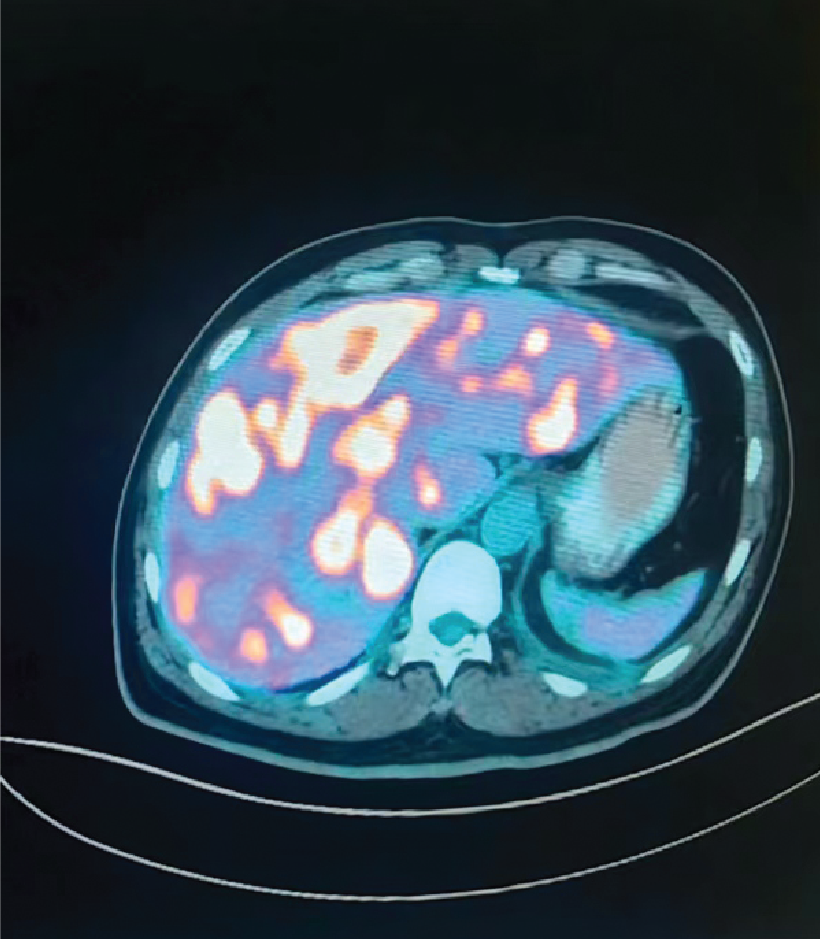

Before Treatment (Lung)

Before Treatment (Liver)